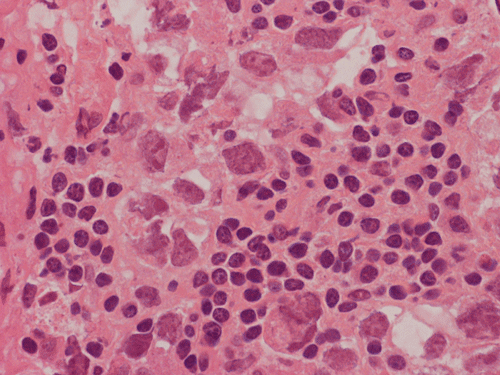

Pathology of the Case: The sample submitted for frozen section has a papillary structure which can be identified as the choroid plexus (Panel C). The center of the choroid plexus is expanded by some large cells accompanied by some smaller cells presumably lymphocytes (Panel D and E). On hematoxylin and eosin stain of the permanent sections, the tumor is composed of clusters of large cells in a background of lymphocytes. On higher magnification, the large cells have enlarged nuclei with prominent nucleoli. No trophoblasts or nor seminomatous component are identified. Immunohistochemistry demonstrated strong positive reactivity for placental alkaline phosphatase (PLAP) (Panel I) and CD117 (c-kit) in the large atypical cells (Panel J). The lymphocytes in the background are strongly immunoreactive for leukocyte common antigen (LCA) (Panel K) but negative for PLAP and CD117.

The discussion here will be limited predominantly to germinoma. Histologically, germinoma has very characteristic features heralded by large, atypical germinoma cells in a background of benign lymphocytes. The germinoma cells are usually huge, with a moderated amount of cytoplasm, and with prominent nucleoli. These cells, even though large, are rarely bizarre. The proportion of germinoma cells with lymphocytes can be highly variable. While most cases show a good mix of both component, the small biopsies yielded by endoscopic biopsy can sample in areas that are lymphocyte predominant or germinoma cell predominant areas which lead to diagnostic pitfalls. It should also be reminded that germinoma has a strong tendency to undergo granulomatous changes. Such granulomatous changes may completely efface the usually big cell-small lymphocyte classic pattern. These biopsies, however, would histologically suggest infection but the clinical history usually would not. Knowing the clinical history is often helpful. Trophoblastic cells could be seen and their presence may indicate a worse prognosis for germinomas. Non-seminomatous component such as embryonal cell carcinoma, yolk sac tumor (endodermal sinus tumor), and choriocarcinoma should also be identified if present.

The germinoma cells are positive for several immunohistochemical markers. These adjuncts are helpful for confirming the diagnosis or when the tumor is composed largely of the large, atypical germinoma cells. The germinoma cells are positive for placental alkaline phosphatase (PLAP) and OCT4 6. They are also positive for CD117 (c-kit) but it should be noted that CD117 is not as specific as PLAP or OCT4.